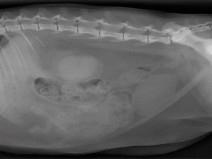

• Soirée Mon chat fait du bruit quand il respire

L'AFVAC Sud-Est vous donne rdv à Montpellier pour une soirée autour des bruits respiratoires chez le chat.

Morgane CANONNE (Dipl. ECVIM-CA), forte de son expérience universitaire, viendra vous présenter une série de cas cliniques autour de l'appareil respiratoire supérieur et profond du chat.